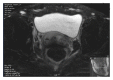

Background. Mullerian duct anomalies (MDAs) are congenital defects of the female genital system that arise from abnormal embryological development of the Mullerian ducts. A didelphys uterus, also known as a "double uterus," is one of the least common amongst MDAs. This report discusses a case of didelphys uterus that successfully conceived, carried her pregnancy to term, and delivered vaginally without any significant complications. Case. Patient is a 29-year-old G2P0010 from Bangladesh, initially came a year prior in her first pregnancy, with spontaneous abortion (SAB). Pelvic Sonogram at that time showed a diagnosis of bicornuate versus didelphys uterus. There were no renal anomalies on subsequent abdominal CT scan. Patient presented with the second pregnancy and had uncomplicated prenatal care and did not have signs of preterm labor; fetus showed appropriate growth and the pregnancy was carried in the left uterus. Patient presented at 38 4/7 wks with Premature Rupture of Membrane and underwent induction of labor with Cytotec. Antibiotics were started for chorioamnionitis. Patient had a vaginal delivery with left mediolateral episiotomy and complete tear of vaginal septum. Third stage of labor was complicated with retained placenta, which was removed manually in the operating room with total EBL of 600 cc.